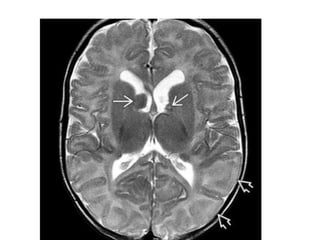

Subependymal Nodules • appearas elevated, rounded, hamartomatous lesions • located beneath the ependymal lining of the lateral ventricles, along the course of the caudate nucleus • Are small(generally < 1.3cm) nodular "bumps" that protrude from the walls of the lateral ventricles. • In the unmyelinated brain, SENs appear hyperintense on T1WI and hypointense on T2WI. With progressive myelination, the SENs gradually become isointense with WM • They often calcify with increasing age • An enhancing or enlarging SEN—especially if located near the foramen of Monro—is suspicious for SEGA. • Calcified SENs appear variably hypointense on T2WI and are especially easy to detect on T2* sequences

• Cortical Tubers –Broad, expanded gyrus – CT: Initially hypodense; Ca++ ↑ with age • 50% of patients eventually develop ≥ 1 calcified tuber(s) – MR: Periphery isointense, subcortical portion T2/FLAIR hyperintense • Subependymal Nodules – CT: Ca++ rare in first year; ↑ with age • 50% eventually calcify • Don't enhance – MR: T1 hyper-, T2 hypointense; 50% enhance • White Matter Lesions – T2/FLAIR hyperintense radial lines/wedges • Subependymal Giant Cell Astrocytoma – CT: Mixed-density mass at foramen of Monro, moderate enhancement – MR: Heterogeneous signal, strong enhancement

• #32 More cephalad scan shows additional hyperintense subependymal nodules as well as multiple hyperintense radial bands extending outward from the lateral ventricles. More cephalad T2WI shows that the thickened radial bands are hypointense relative to the unmyelinated white matter. tubers appear as thickened hyperintense cortex compared to the underlying unmyelinated WM on T1WI and become moderately hypointense on T2WI. "Streaky" linear or wedge-shaped T2/FLAIR hyperintense bands may extend from the tuber all the way through the WM to the ventricular ependyma

• #34 T2WI shows that the WM is largely unmyelinated. The SENs are isointense with gray matter. Cortical tubers have poor GM-WM delineation.